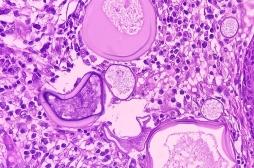

tumeur

LES MALADIES